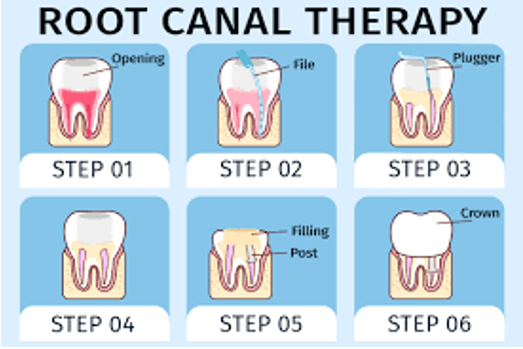

Τι είναι η πολφεκτομή ή απονεύρωση;